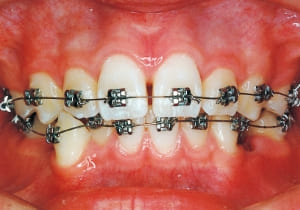

2 After Phase 2 Treatment 6-6-’94

This was a case of significant Protruding upper bite, and early treatment was deemed necessary from a functional perspective.

Although the treatment spanned a long period of 8.5 years from the initial visit to the removal of the retainer, such a treatment duration is required when initiating treatment early. This case raised numerous issues, including whether to utilize growth for treatment and determining the optimal timing for treatment initiation.

The first phase of treatment involved extracting the left and right maxillary deciduous canines. The space created was used to forcibly retract the four anterior teeth, thereby aiming to improve lip closure function (6–9, 11). Morphological changes suggest that lip function differed before and after treatment (6, 9). Subsequently, the first premolars erupted, but extraction is planned to secure space for canine eruption (10). A Class II molar relationship remains, but the significant overjet has improved (11).

In the maxilla, insufficient space for canine eruption was inevitable, necessitating extraction as part of the treatment plan. The maxillary first premolars on both sides were extracted during routine observation to create space for canine eruption (14). Eventually, the canines erupted and settled into relatively favorable positions (15,19,20). In the mandibular dentition, crowding was also present, leading to extraction of the mandibular first premolars on both sides. Treatment with full bracket was then initiated (17).

The facial type changed from backward divergent to straight between the initial visit and after retention (27–31). Cephalometric X-rays reveal significant mandibular growth (32).

Treatment period from initiation to completion of active treatment lasted 6 years and 2 months, with appliances worn for 3 years and 8 months of that time. Retention lasted 2 years and 2 months following active treatment.